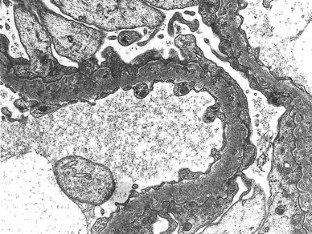

We describe a 24-year-old woman with a distinctive glomerular lesion. She presented with nephrotic syndrome and the diagnosis of systemic lupus erythematosus was made on the basis of laboratory and clinical findings. Renal biopsy showed a bubbling appearance of the glomerular capillary wall indicating lupus nephritis class V. On an electron microscopy, the glomerular basement membrane (GBM) was irregularly thickened and contained abundant vesicular and microtubular bodies. In addition, there were many epithelial foot processes infolding into the GBM. A few small deposits were observed beneath the foot processes and around the vesicular and microtubular bodies. Although the clinicopathological significance of podocytic infolding has not been fully elucidated, it may be a novel morphological entity in the glomerulonephritides.

Fig. 2